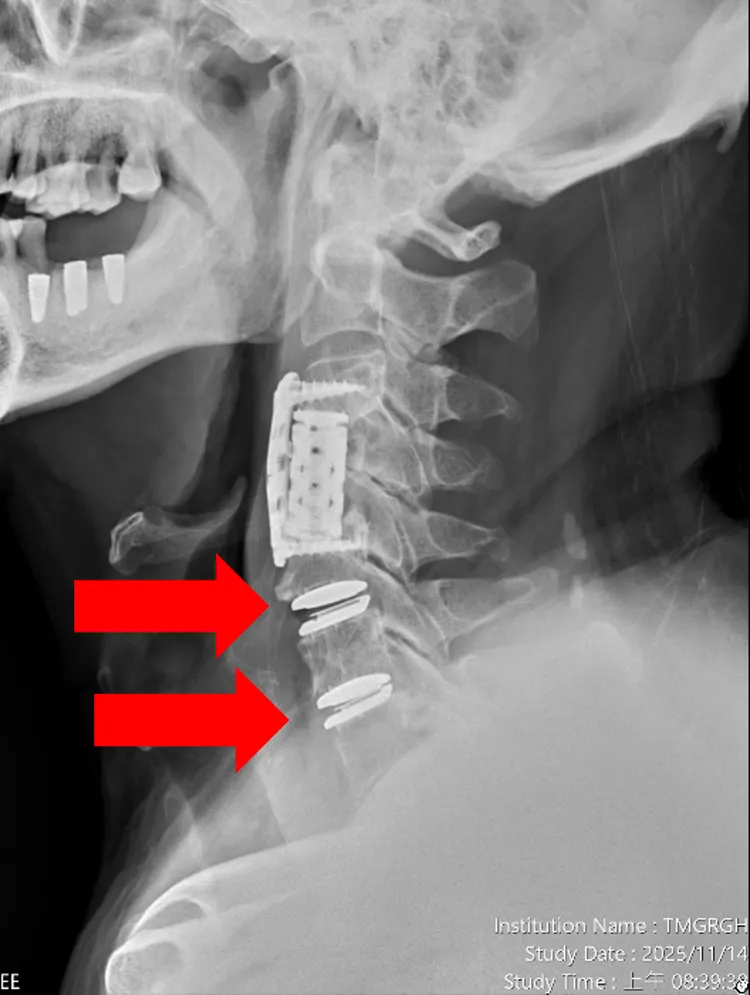

患者的第五第六及第六第七頸椎間盤切除,並植入人工椎間盤,症狀大幅改善。院方提供

李漢忠根據脊椎中心跨團隊精準檢查結果,建議患者進行「第五至第七節頸椎椎間盤切除併人工椎間盤置換」,並同步施作「右手正中神經減壓」。手術歷時約兩小時,出血僅 50c.c,搭配高規格顯微鏡、導航影像系統及超高速電鑽,大幅降低手術風險,加速恢復,不需佩戴頸圈。